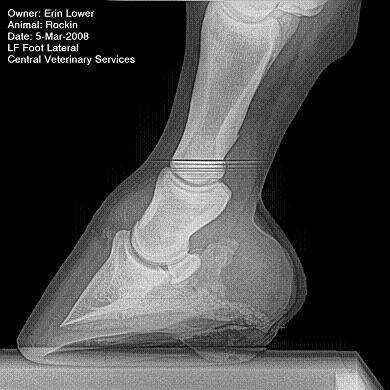

So, Rockin's x-rays were sent to a radiologist and he confirmed "normal" changes in the navicular bones for a horse her age, but slightly more significant ones in the right (sore) foot.

She also has sidebone in both fronts, but apparently that isn't causing any discomfort.

Finally, she has a "small chronic exostosis on the lateral aspect of the proximal phalanx" which, according to the radiologist, shouldn't be causing discomfort but I have read that these can be mild-to-moderately painful... I wouldn't mind another opinion on that.

I will attach as many images as possible from her x-rays (there are many different views). I don't have any pics of the feet as someone deleted them from my camera before I could download them. I'll try to take pics next time she is trimmed. Please, anyone with knowledge of hooves, give any opinions that you might have (especially Dr. O!)

I cannot rule out lesions based on these images but I will take your radiologist's word that he does not see significant lesions. The exostosis on the RF would be above the level of a well conducted PDN which I believed blocked the lameness before?